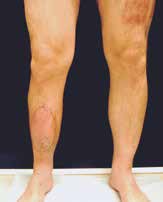

Nach einem kindlichen Trauma entwickelte ein 36-jähriger Mann eine chronische Tibiaschaftosteitis mit großer Defektwunde. Die Sanierung der Staphylococcus-aureus-positiven Osteitis erfolgte durch unfallchirurgische serielle Debridements der Knochen und Weichteile (Abb. 1a) und durch lokale und systemische Antibiotikagabe. Nach dreifach negativen Abstrichen wurden die durch die Markraumausfräsung entstandenen Tibiadefekte (Abb. 1b) mit einer an der A. tibialis posterior vaskularisierten, segmentierten Fibula (Abb. 1c) rekonstruiert. Um den Integumentdefekt neben der Fibulamonitorinsel und die freiliegende Tibia komplettierend zu decken, wurde an das distale Ende der A. fibularis des Knochentransplantats ein freier M.-gracilis-Muskellappen angeschlossen; die Fibula diente somit als Durchflusslappenplastik (Abb. 1d). Die Knochentransplantate wurden mit Einzelschraubenosteosynthesen gesichert und zeigen zehn Wochen postoperativ bereits Zeichen einer knöchernen Einheilung (Abb. 1e). Der Heilungsverlauf der Integumentrekonstruktion gestaltete sich ebenfalls unauffällig (Abb. 1f). Nach dreimonatiger Entlastung an Unterarmgehstützen und sechsmonatiger Kompressionsstrumpftherapie geht der Patient inzwischen volllastig ohne Gehhilfen.